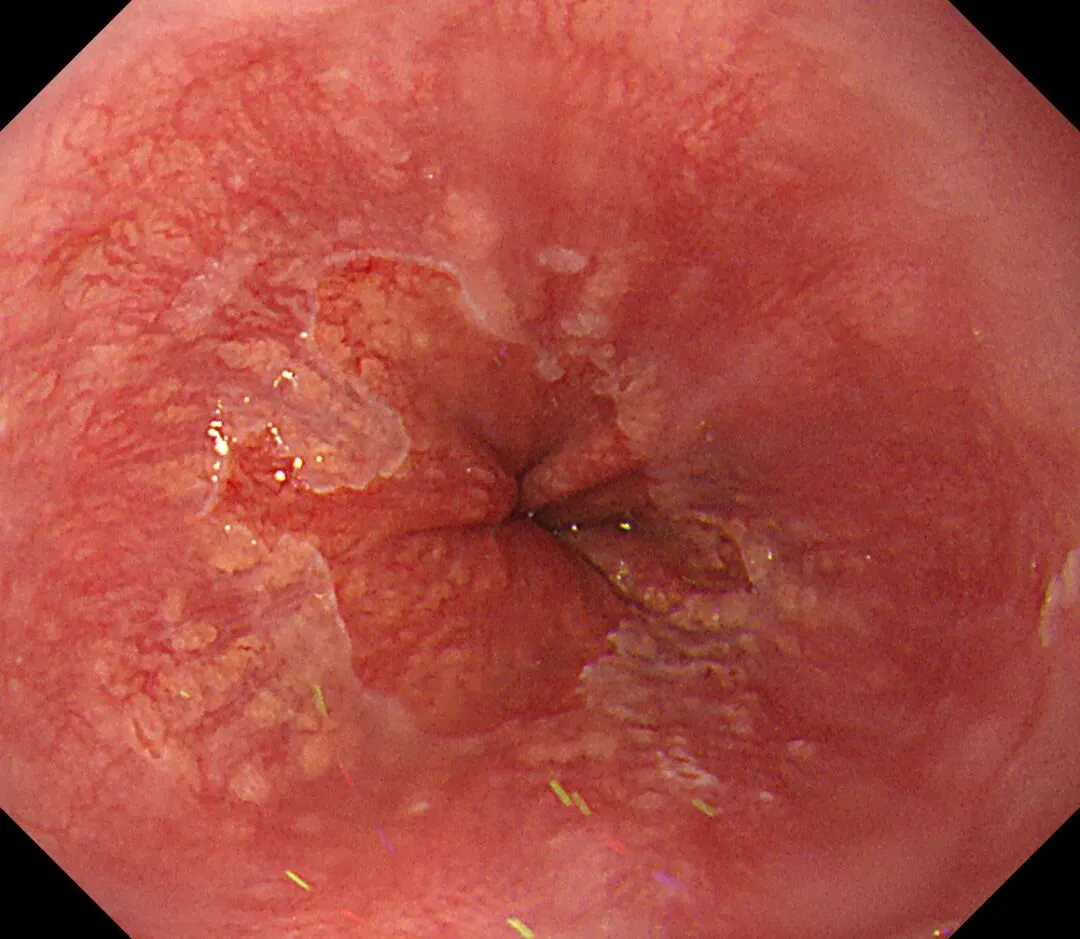

这一期不用码字,挺好的,很可惜一直没机会听过胡导讲的关于这个“花环征”的大课,学习内容来源于雨夜大师的号花环征:AIG背景的胃食管结合部的黄色颗粒状隆起及半透明“泡状”改变

补充自己在两例A型胃炎/AIG 观察到的“花环征”,巩固下学习效果。。。

case1:

1.白光表现为胃食管交界处黄色颗粒状隆起及半透明“泡状”改变

2.窄带光下可见颗粒状隆起呈褐色改变,放大可见细微网状血管结构及半透明“泡状”改变

3.典型病理是鳞状上皮局灶性变薄及黏膜固有层显著增生、扩张的贲门腺。